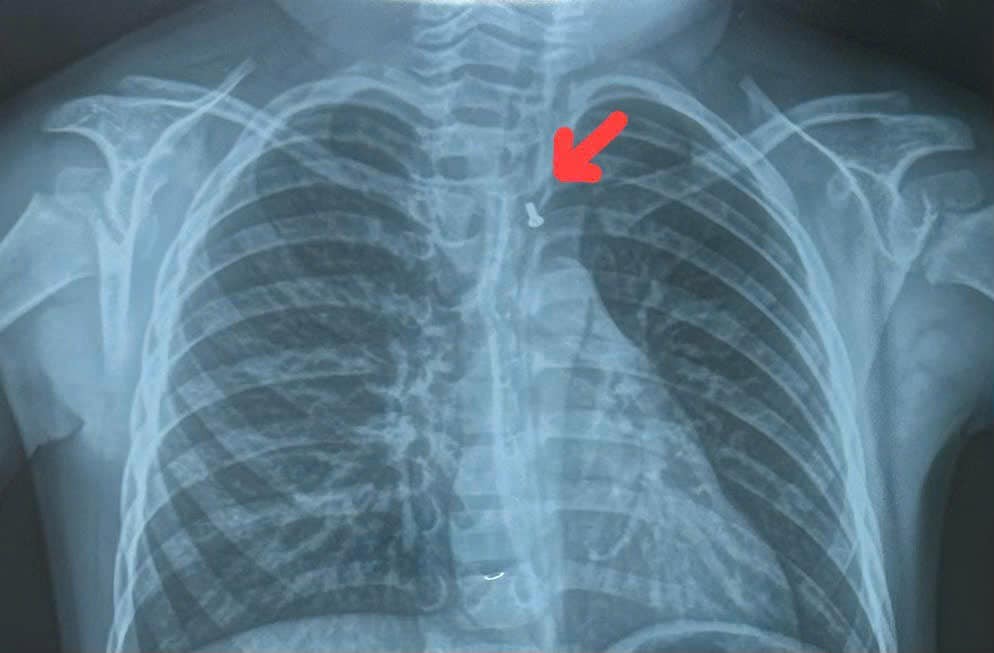

Cùng ngày, Bệnh viện Đa khoa Xuyên Á cho biết, tại đây cũng vừa tiếp nhận cấp cứu gắp dị vật là mảnh kim loại tròn, kích thước 17mm kẹt ở vùng hạ họng của bé trai T.P.T. (30 tháng tuổi, ngụ tại tỉnh Đồng Tháp). Trước đó, bệnh nhi đã ngậm mảnh kim loại trong miệng, khi chơi đùa đã vô thức nuốt dị vật, ngay lập tức trẻ rơi vào tình trạng khó thở, đau ở vùng họng, nôn ói.

Bằng phương pháp nội soi, các bác sĩ đã lấy thành công dị vật ra ngoài. Tuy nhiên, mảnh kim loại sắc nhọn đã gây tổn thương thực quản, phải tiếp tục theo dõi, điều trị để tránh nguy cơ biến chứng có thể xảy ra.

Dị vật là mảnh kim loại gây tổn thương thực quản cho bé trai 30 tháng tuổi